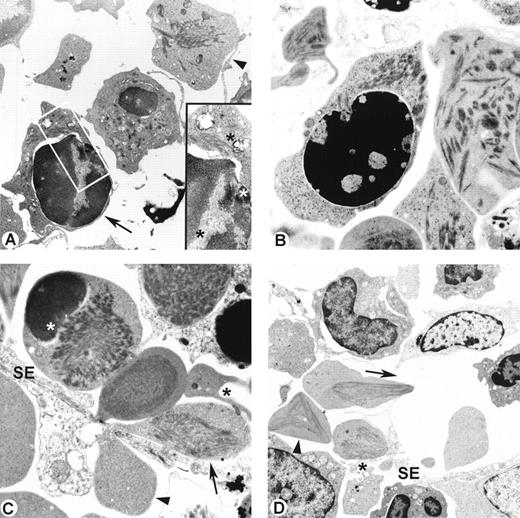

To investigate the erythropoietic/hematopoietic mechanisms in SCD, we first have undertaken several morphologic studies in the SAD transgenic model. Histologic and ultrastructural analysis of bone marrow showed a large proportion of nucleated erythroid precursors (pronormoblast, normoblast); the marked erythroid hyperplasia showed a reversal of the usual 1:3 erythroid:myeloid ratio to an erythroid increase of at least 1:1 in all transgenic SAD and SAD/βd3 mice. Identification of the erythroid cell type was based on ultrastructural morphologic changes in both the pattern of nuclear chromatin and electron density of cytoplasm.24,25 Pronormoblasts and basophilic normoblasts, which are identified by their characteristic open chromatin pattern, large cell size, and abundance of cytoplasmic organelles, were frequently found in mitosis, consistent with a state of accelerated erythropoiesis (data not shown). These early erythroid precursors showed no pathologic alterations and did not contain hemoglobin polymers. In contrast, polychromatophilic normoblasts, identified by increased chromatin condensation and higher cytoplasmic density, were the earliest erythroid precursors to demonstrate hemoglobin polymers, which is probably related to their higher intracellular hemoglobin content compared with the earlier differentiation stages (Fig 1A). Polymers were identified in 21% ± 5% of polychromatophilic normoblasts in the marrow matrix of SAD mice (Table 1). Cytoplasmic polymers were arranged in small bundles, most often limited to one region of the cytoplasm (Fig 1A and B). In late normoblasts, the cell membrane was frequently stretched and deformed by underlying polymer bundles. Interestingly, polymers were present not only in the cytoplasm, but also in the interchromatin regions of the nucleus (Fig 1A, inset). Polymer fibers were occasionally seen extending from cytoplasm into the nucleus, apparently through the nuclear pores at sites where invagination of the nuclear envelope was observed (Fig 1B), and upon enucleation, polymer fibers were sometimes retained in extruded nuclei (Fig 1A). Large conglomerates of polymer fibers (Fig 1C and D) were also identified in 43% ± 10% of the more mature erythroid reticulocytes in the marrow matrix of SAD mice (Table 1). Reticulocytes (Fig 1A through D) were distinguished from erythrocytes by their larger cell size and clear cytoplasm and the presence of cytoplasmic organelles such as ribosomes and mitochondria. During migration of reticulocytes from the marrow matrix through the sinusoidal endothelium to enter the circulation, large amounts of polymers were detected in the reticulocyte portion that remained in the extravascular matrix while the engaged intravascular portion was often devoided of polymers (Fig1C), consistent with the differential oxygen levels between both sides.26 Alternatively, this peculiar distribution pattern of polymers could be related to a mechanical effect whereby polymer fibers could be retained in the extravascular portion during the passage. These SAD reticulocytes passing through the narrow fenestrae of the sinusoidal barrier also showed marked morphologic deformation. Moreover, the occurrence of frequent cellular fragments highly suggestive of reticulocyte fragmentation were observed in sites adjacent to the egressing polymerized and deformed reticulocytes. These types of fragments were never seen in nontransgenic control animals. Most likely, the observed fragmentation suggests that hemoglobin polymerization caused an increased cell fragility. Furthermore, a majority of the medullary macrophages were involved in active phagocytic clearance of the fragmented as well as intact polymerized reticulocytes. Whereas cells from the erythroid lineage present several anomalies, cells from the myeloid and megakaryocytic lineages appeared to be ultrastructurally normal in SAD mice.

(A) Polychromatophilic normoblast and reticulocyte in bone marrow of SAD mouse. Parallel bundles of polymer fibers are noted in the cell periphery (arrow) of polychromatophilic normoblast and in cytoplasm of reticulocyte (arrowhead; original magnification × 6,372). Inset shows polymer bundles (star) in the cytoplasm as well as in the interchromatin regions of the extruding nucleus (original magnification × 18,720). (B) Polychromatophilic normoblast in bone marrow of SAD mouse showing cytoplasmic and nuclear polymer bundles with indentation of the nuclear envelope (original magnification × 10,000). (C) Reticulocyte in bone marrow of SAD/βd3 mouse migrating through narrow gap in sinusoidal endothelium (SE). Polymers are restricted to the extravascular portion of the cytoplasm (arrow) compared with the intravascular portion (arrowhead) of a markedly deformed reticulocyte. An erythroid cell fragment (black star) is present next to migrating reticulocyte. A dense chromatin-like cap, probably a retained nuclear fragment, is seen involving part of the cell periphery of a polymerized reticulocyte (white star). No polymers are seen in intravascular erythrocytes. (original magnification × 7,500). (D) Reticulocyte traversing a wide gap in the sinusoidal barrier (SE), showing pointed extensions with polymer bundles oriented in the direction of the flow (arrow). A large geometric conglomerate of polymer bundles is seen in adjacent extravascular reticulocytes (arrowhead). Reticulocyte fragments (black star) are present next to reticulocyte in process of migrating through a narrow gap. Polymers are absent in the intravascular erythrocyte (original magnification × 3,000).

To determine whether the polymerization characteristics of the erythroid cell lineage were affected by the intracellular sickle hemoglobin concentrations, we have compared the SAD mice erythrons (19% hemoglobin SAD) with those of the SAD/βd3 mice (26% hemoglobin SAD).17 Previous analysis of mature RBCs of SAD/βd3 mice showed balanced hemoglobin chains and did not show any of the ultrastructural features described in human β-thalassemia, such as Heinz bodies, remnants of membranes or organelles, or iron accumulation.18 In comparison with SAD mice, polymers were observed in a significantly larger proportion of differentiating erythroid cells in SAD/βd3 mice: 36% ± 6% for late normoblasts and 62% ± 14% for reticulocytes (Table 1). Higher levels of hemoglobin SAD in erythroid cells thus appear to induce a higher number of cells with polymer fibers. However, the polymer structures were similar in diameter and length for both SAD and SAD/βd3 mice, as previously documented.18